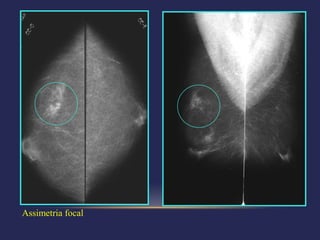

Assimetria focal   Compressão localizada

 Categoria 3 – achado provavelmente

 Achados típicos:

 Nódulo sólido, circunscrito, não-calcificado

 Assimetria focal

 Agrupamento de calcificações redondas

Assimetria focal